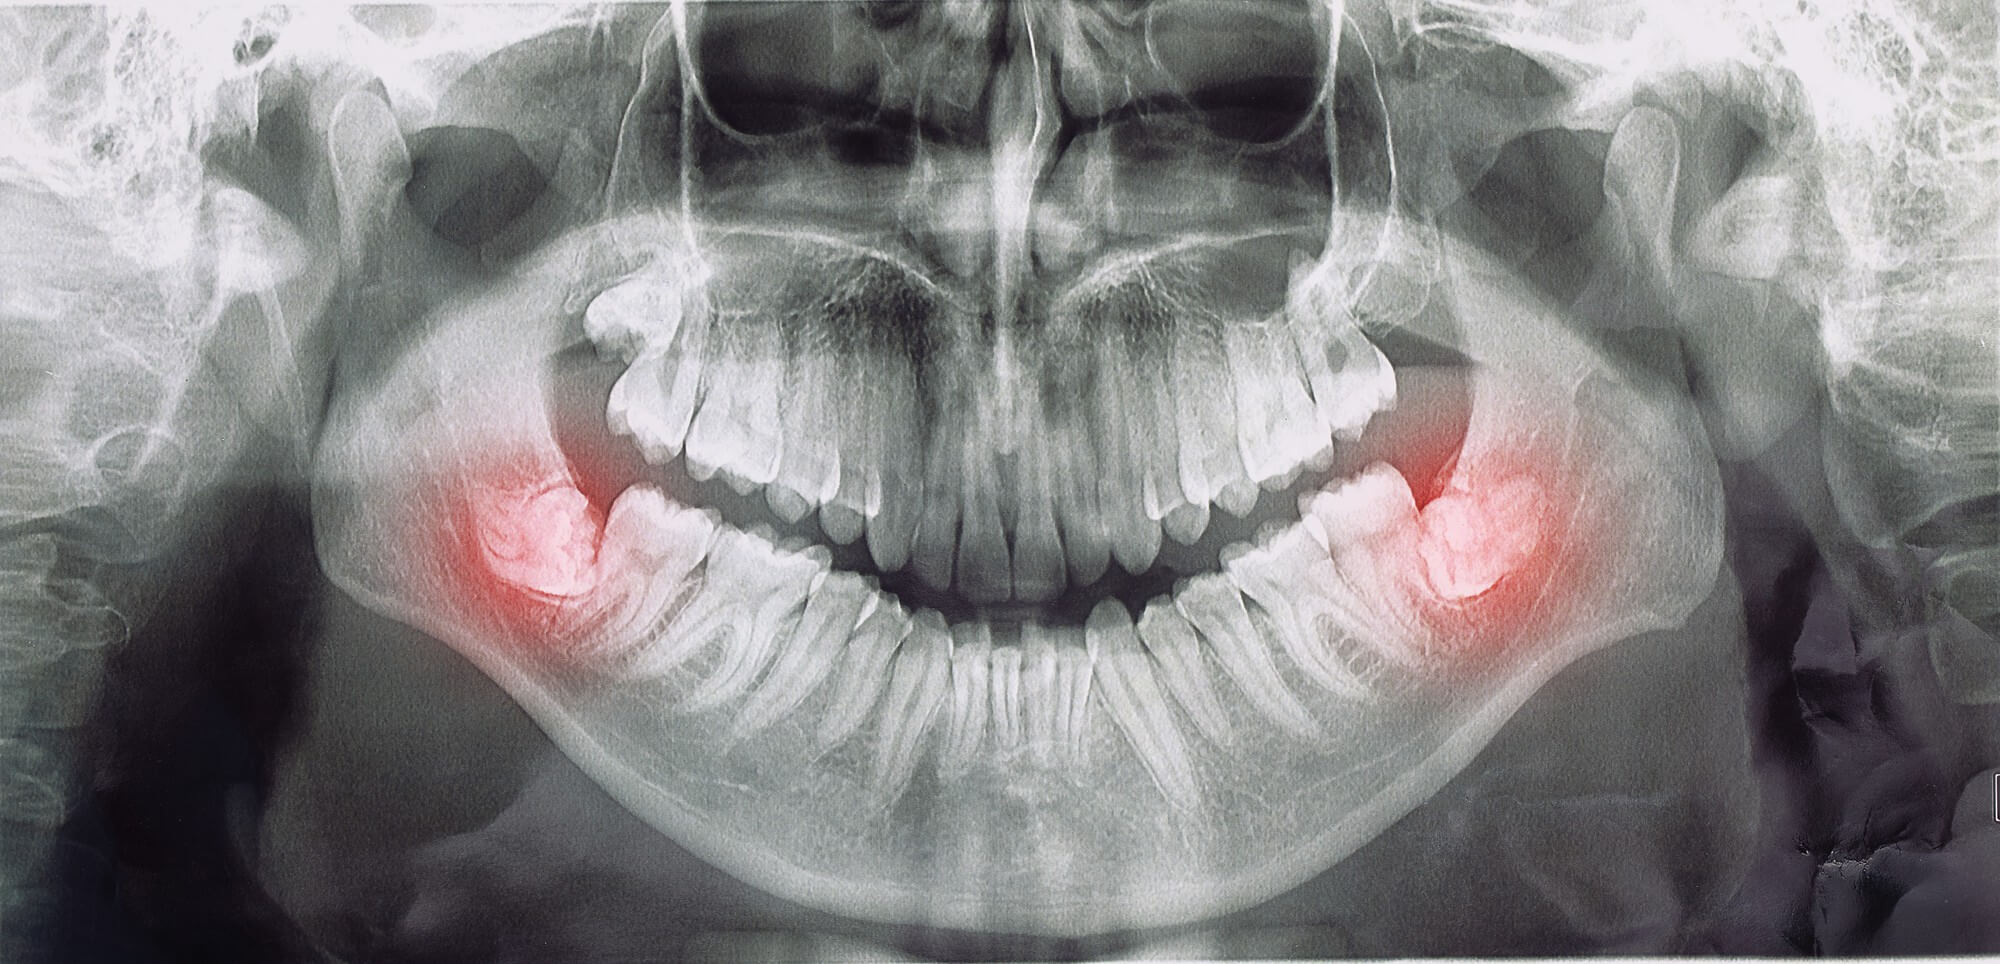

Wisdom teeth often cause problems because most mouths don't have enough room to accommodate them. When they emerge, they can push against neighboring teeth, cause crowding, become impacted (trapped beneath the gumline), or create hard-to-clean areas that lead to tooth decay.

Before the procedure, we take digital X-rays to assess the position of your wisdom teeth and how many you have (most people have between one and four). You'll be placed under anesthesia nitrous oxide or IV sedation, depending on your case for your comfort throughout the procedure.

Not all extractions are the same. A simple extraction involves removing a visible tooth that has fully erupted. A surgical extraction is required for teeth that are impacted (partially or fully beneath the gumline), or when a tooth has broken and only a root remains.